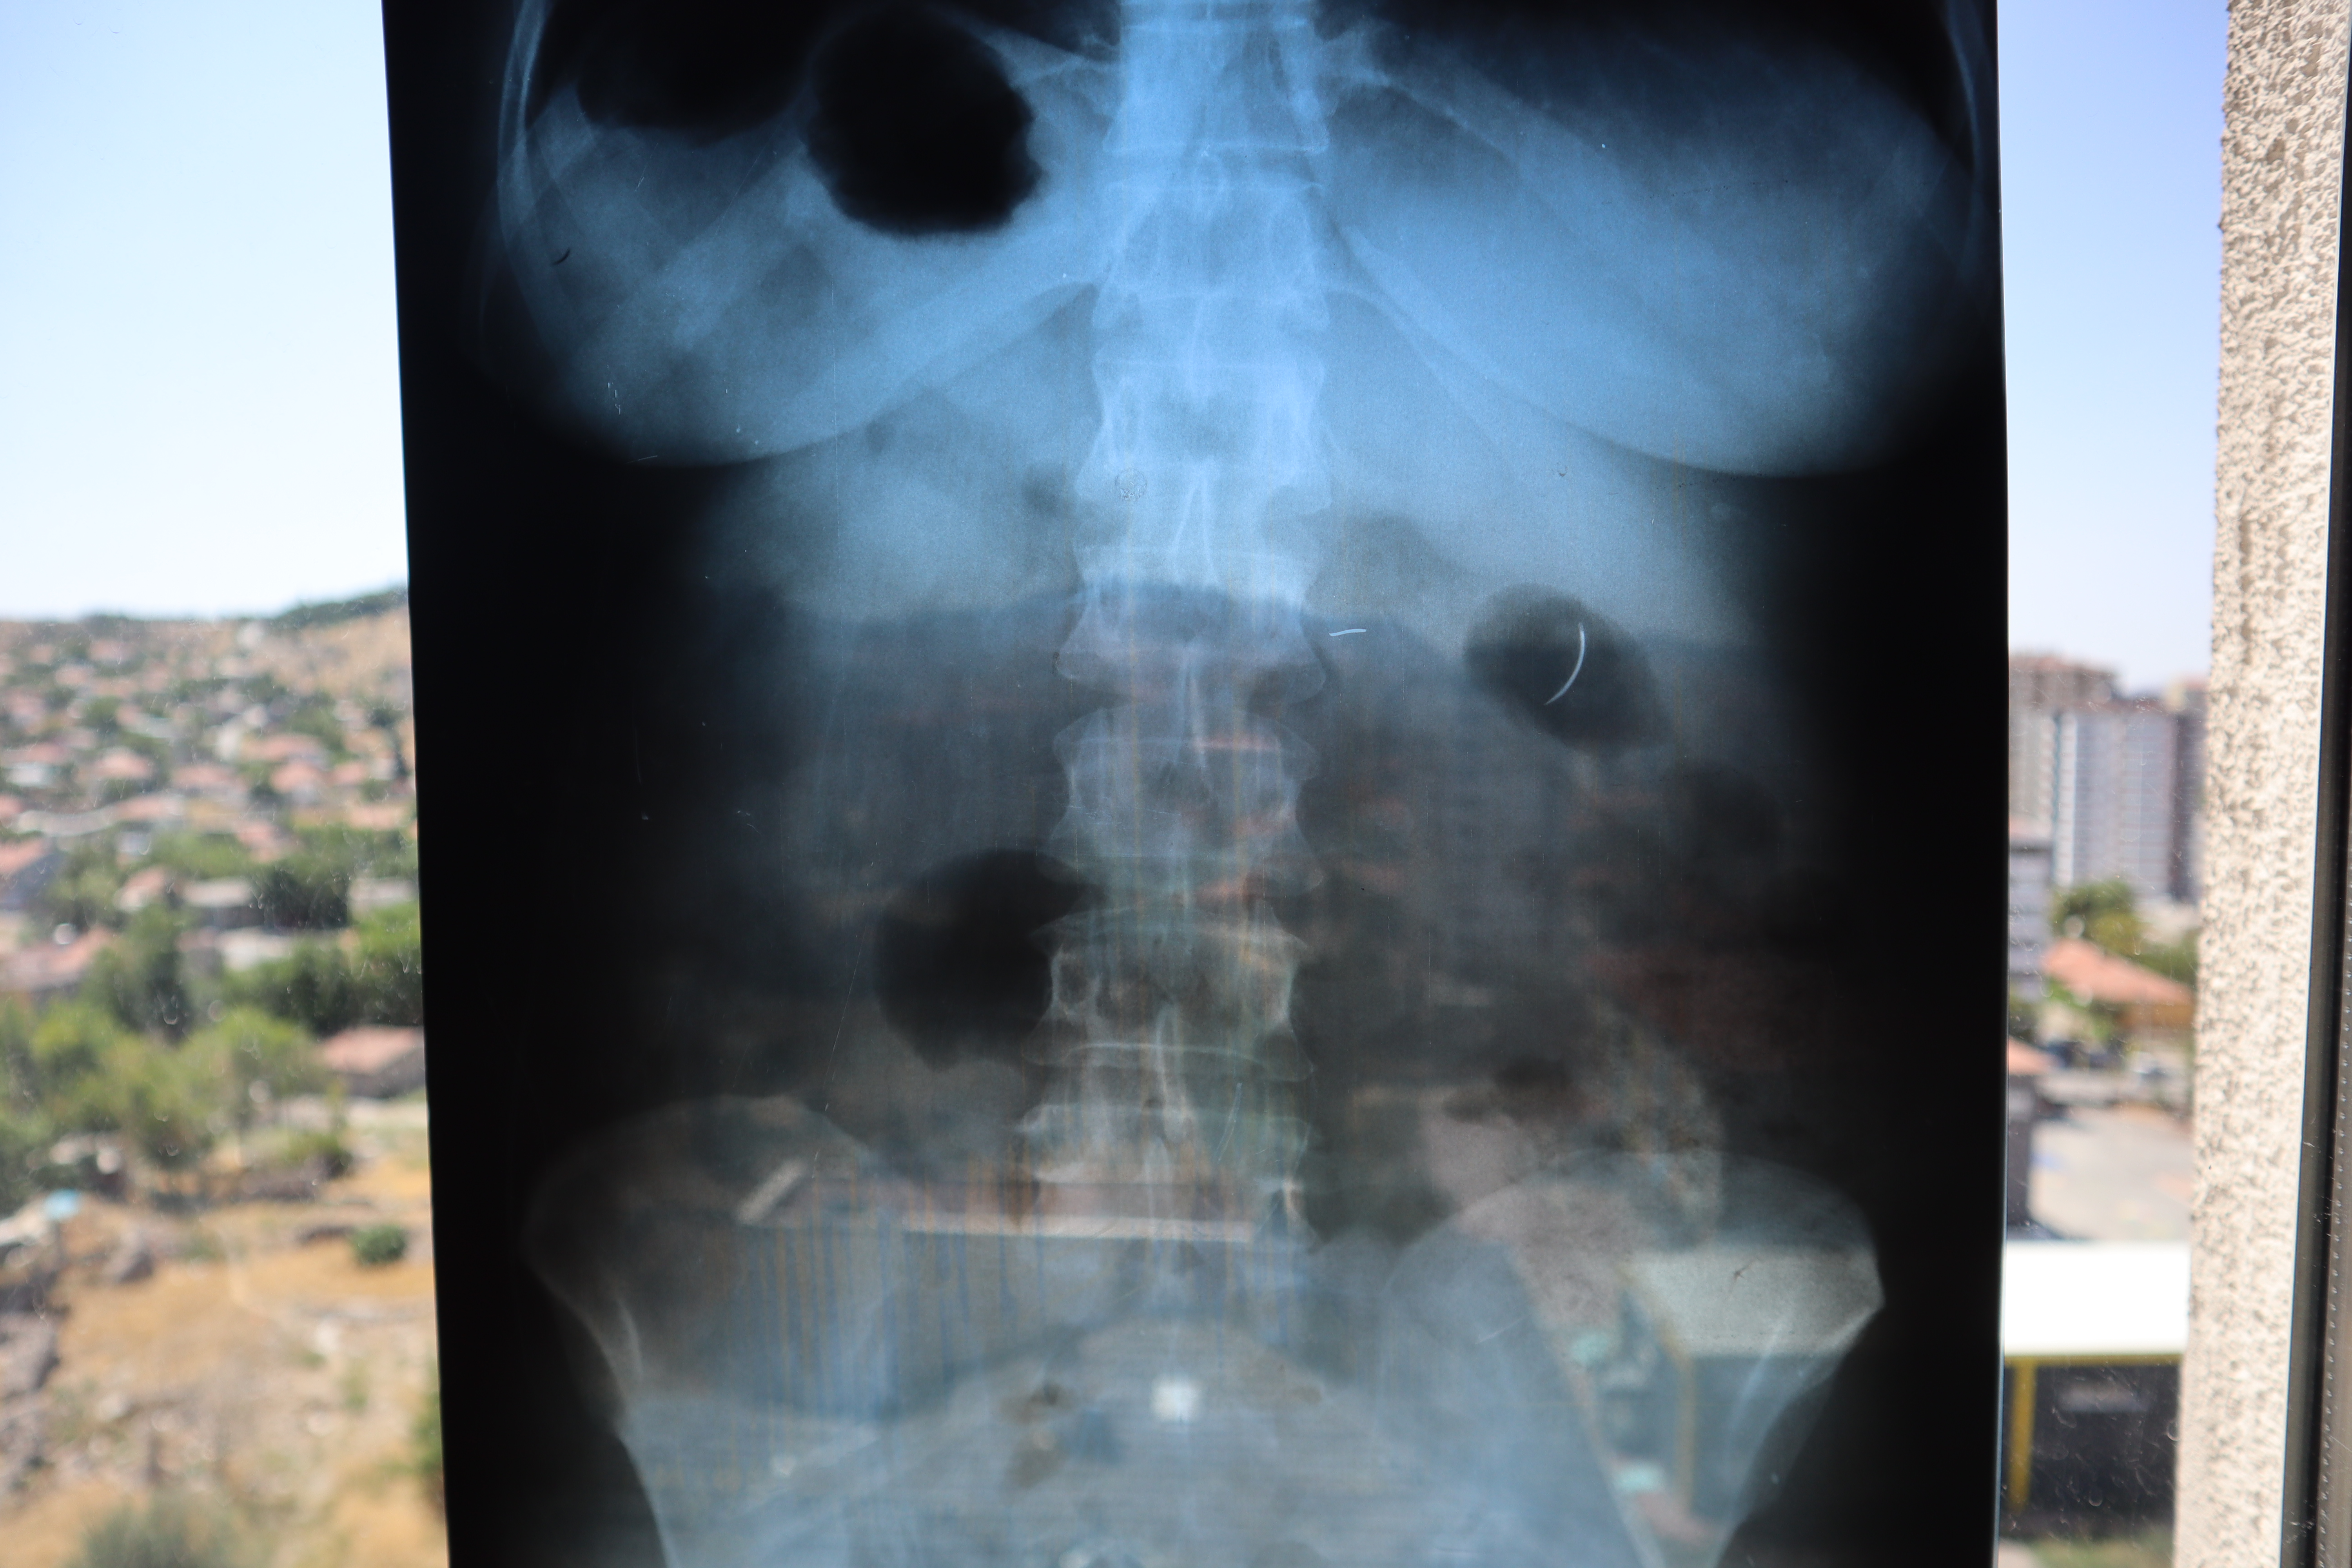

Kentte yaşayan 2 çocuk annesi Ayhan Tanyıldız, 2003 yılında karaciğerindeki kist nedeniyle ameliyat oldu. Ameliyat olduktan 6 yıl sonra böbrek rahatsızlığı nedeniyle hastaneye giden Tanyıldız’ın çekilen röntgeninde iğne görüldü. Tanyıldız’ın kist ameliyatı sırasında karnında ameliyat iğnesi unutulduğu ortaya çıktı. Kendisini özel hastanede ameliyat eden Genel Cerrahi Doktoru İ.D.’ye dava açan Tanyıldız, ağrılarının nedeninin karnında unutulan ameliyat iğnesi olduğunu öğrendi. 19 yıl sonra mahkemesi de sonuçlanan Tanyıldız, bir miktar tazminat almaya hak kazandı. 22 yıldır ameliyat iğnesiyle yaşayan Tanyıldız, “2003 yılında ameliyatım yapıldı. Karaciğerimdeki kistten dolayı ameliyat oldum. Karaciğerimde kist oluşmuş. Kisti alırken ameliyat iğnesini unutmuşlar. 6 yıl sonra fark ettim. İlk öğrendiğimde başka doktora gittim, böbreklerimden rahatsızlanmıştım. Doktor film çekince ‘sen MR’a girme, ciğerinde iğne var’ dedi. O zaman fark ettim. Fiziksel olarak hala ağrısını, yıllardır çekiyorum” diye konuştu.'